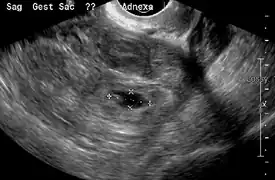

Transvaginal ultrasonography

An ultrasound showing a gestational sac with fetal heart in the fallopian tube has a very high specificity of ectopic pregnancy. It involves a long, thin transducer, covered with the conducting gel and a plastic/latex sheath and inserted into the vagina.[32] Transvaginal ultrasonography has a sensitivity of at least 90% for ectopic pregnancy.[5] The diagnostic ultrasonographic finding in ectopic pregnancy is an adnexal mass that moves separately from the ovary. In around 60% of cases, it is an inhomogeneous or a noncystic adnexal mass sometimes known as the "blob sign". It is generally spherical, but a more tubular appearance may be seen in case of hematosalpinx. This sign has been estimated to have a sensitivity of 84% and specificity of 99% in diagnosing ectopic pregnancy.[5] In the study estimating these values, the blob sign had a positive predictive value of 96% and a negative predictive value of 95%.[5] The visualization of an empty extrauterine gestational sac is sometimes known as the "bagel sign", and is present in around 20% of cases.[5] In another 20% of cases, there is visualization of a gestational sac containing a yolk sac or an embryo.[5] Ectopic pregnancies where there is visualization of cardiac activity are sometimes termed "viable ectopic".[5]

A pregnancy not in the uterus[33]

The combination of a positive pregnancy test and the presence of what appears to be a normal intrauterine pregnancy does not exclude an ectopic pregnancy, since there may be either a heterotopic pregnancy or a "pseudosac", which is a collection of within the endometrial cavity that may be seen in up to 20% of women.[5]